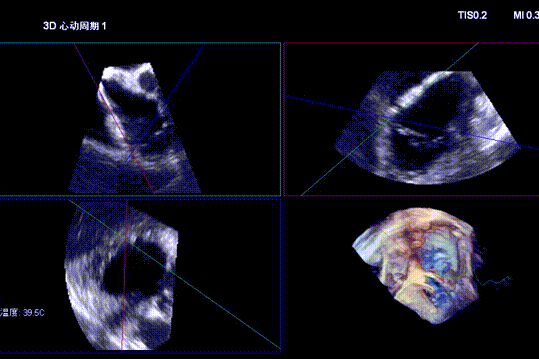

Echocardiographic Assessment:

- Massive tricuspid regurgitation (5+, mean vena contracta 14mm);

- Regurgitant orifices located at antero-septal, central, and postero-septal regions, with a significant gap at the antero-septal region (antero-septal gap 9.1mm), leaflet tethering (tethering height approximately 9mm);

- Tricuspid annular dilation (mean annulus diameter: 43mm);

Preoperative